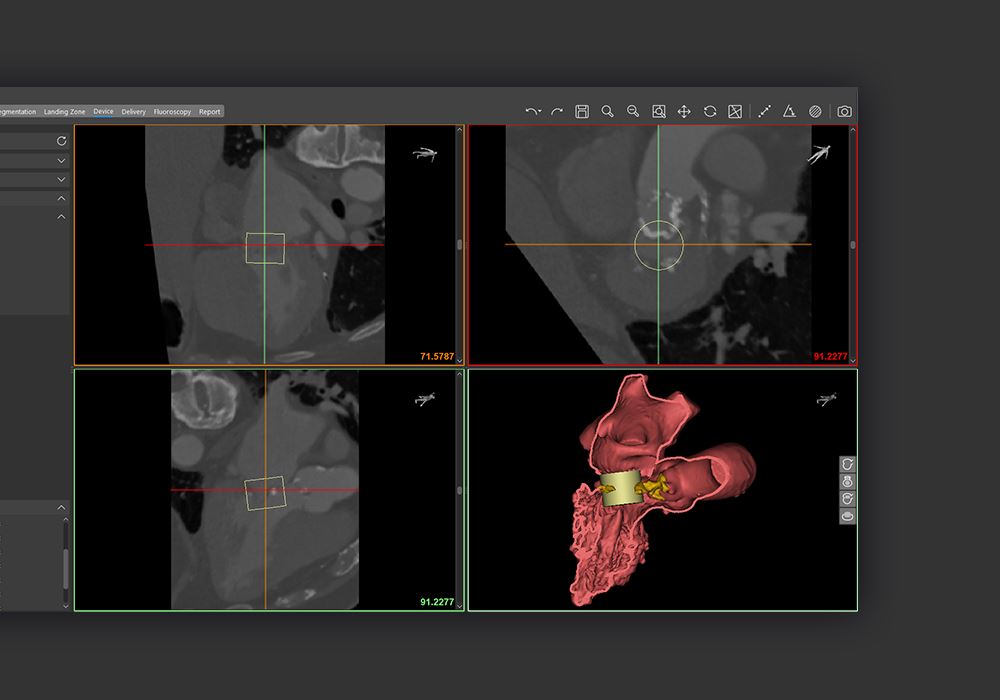

Materialise Enlightens Medical Care With FDA-Approved Cardiovascular Software

Materialise has received FDA clearance for its cardiovascular planning software.